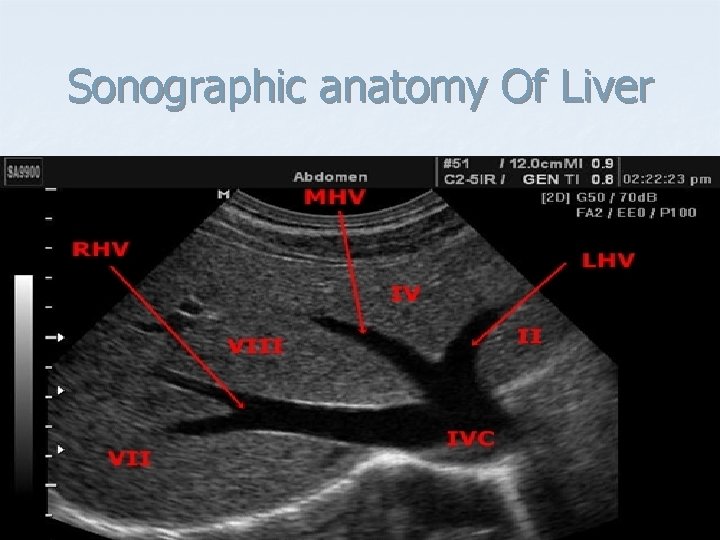

Sonographic anatomy Of Liver